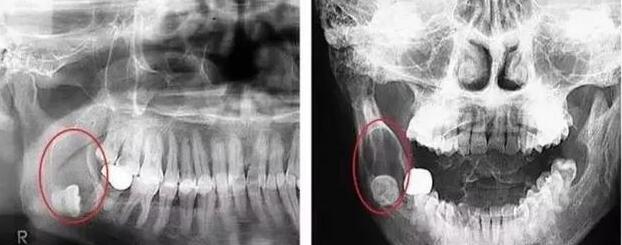

牙在颌骨内由于位置不当,不能萌出到正常咬合位置,被称为阻生牙或阻生齿,常见的就是智齿阻生。阻生牙和覆盖在它上面的牙龈之间,很容易藏污纳垢,孳生细菌,引起口臭、龋坏,当身体抵抗力下降时,常常会发生炎症。阻生牙牙冠周围的牙龈常常会发炎,疼痛,严重时脸颊可以肿胀,张口困难,甚至全身发热,颌下淋巴结肿大。阻生牙常常还会引起邻牙龋坏,松动,牙槽骨吸收等症状。因此对于阻生牙应该及早拔除。广州拔牙哪家好?